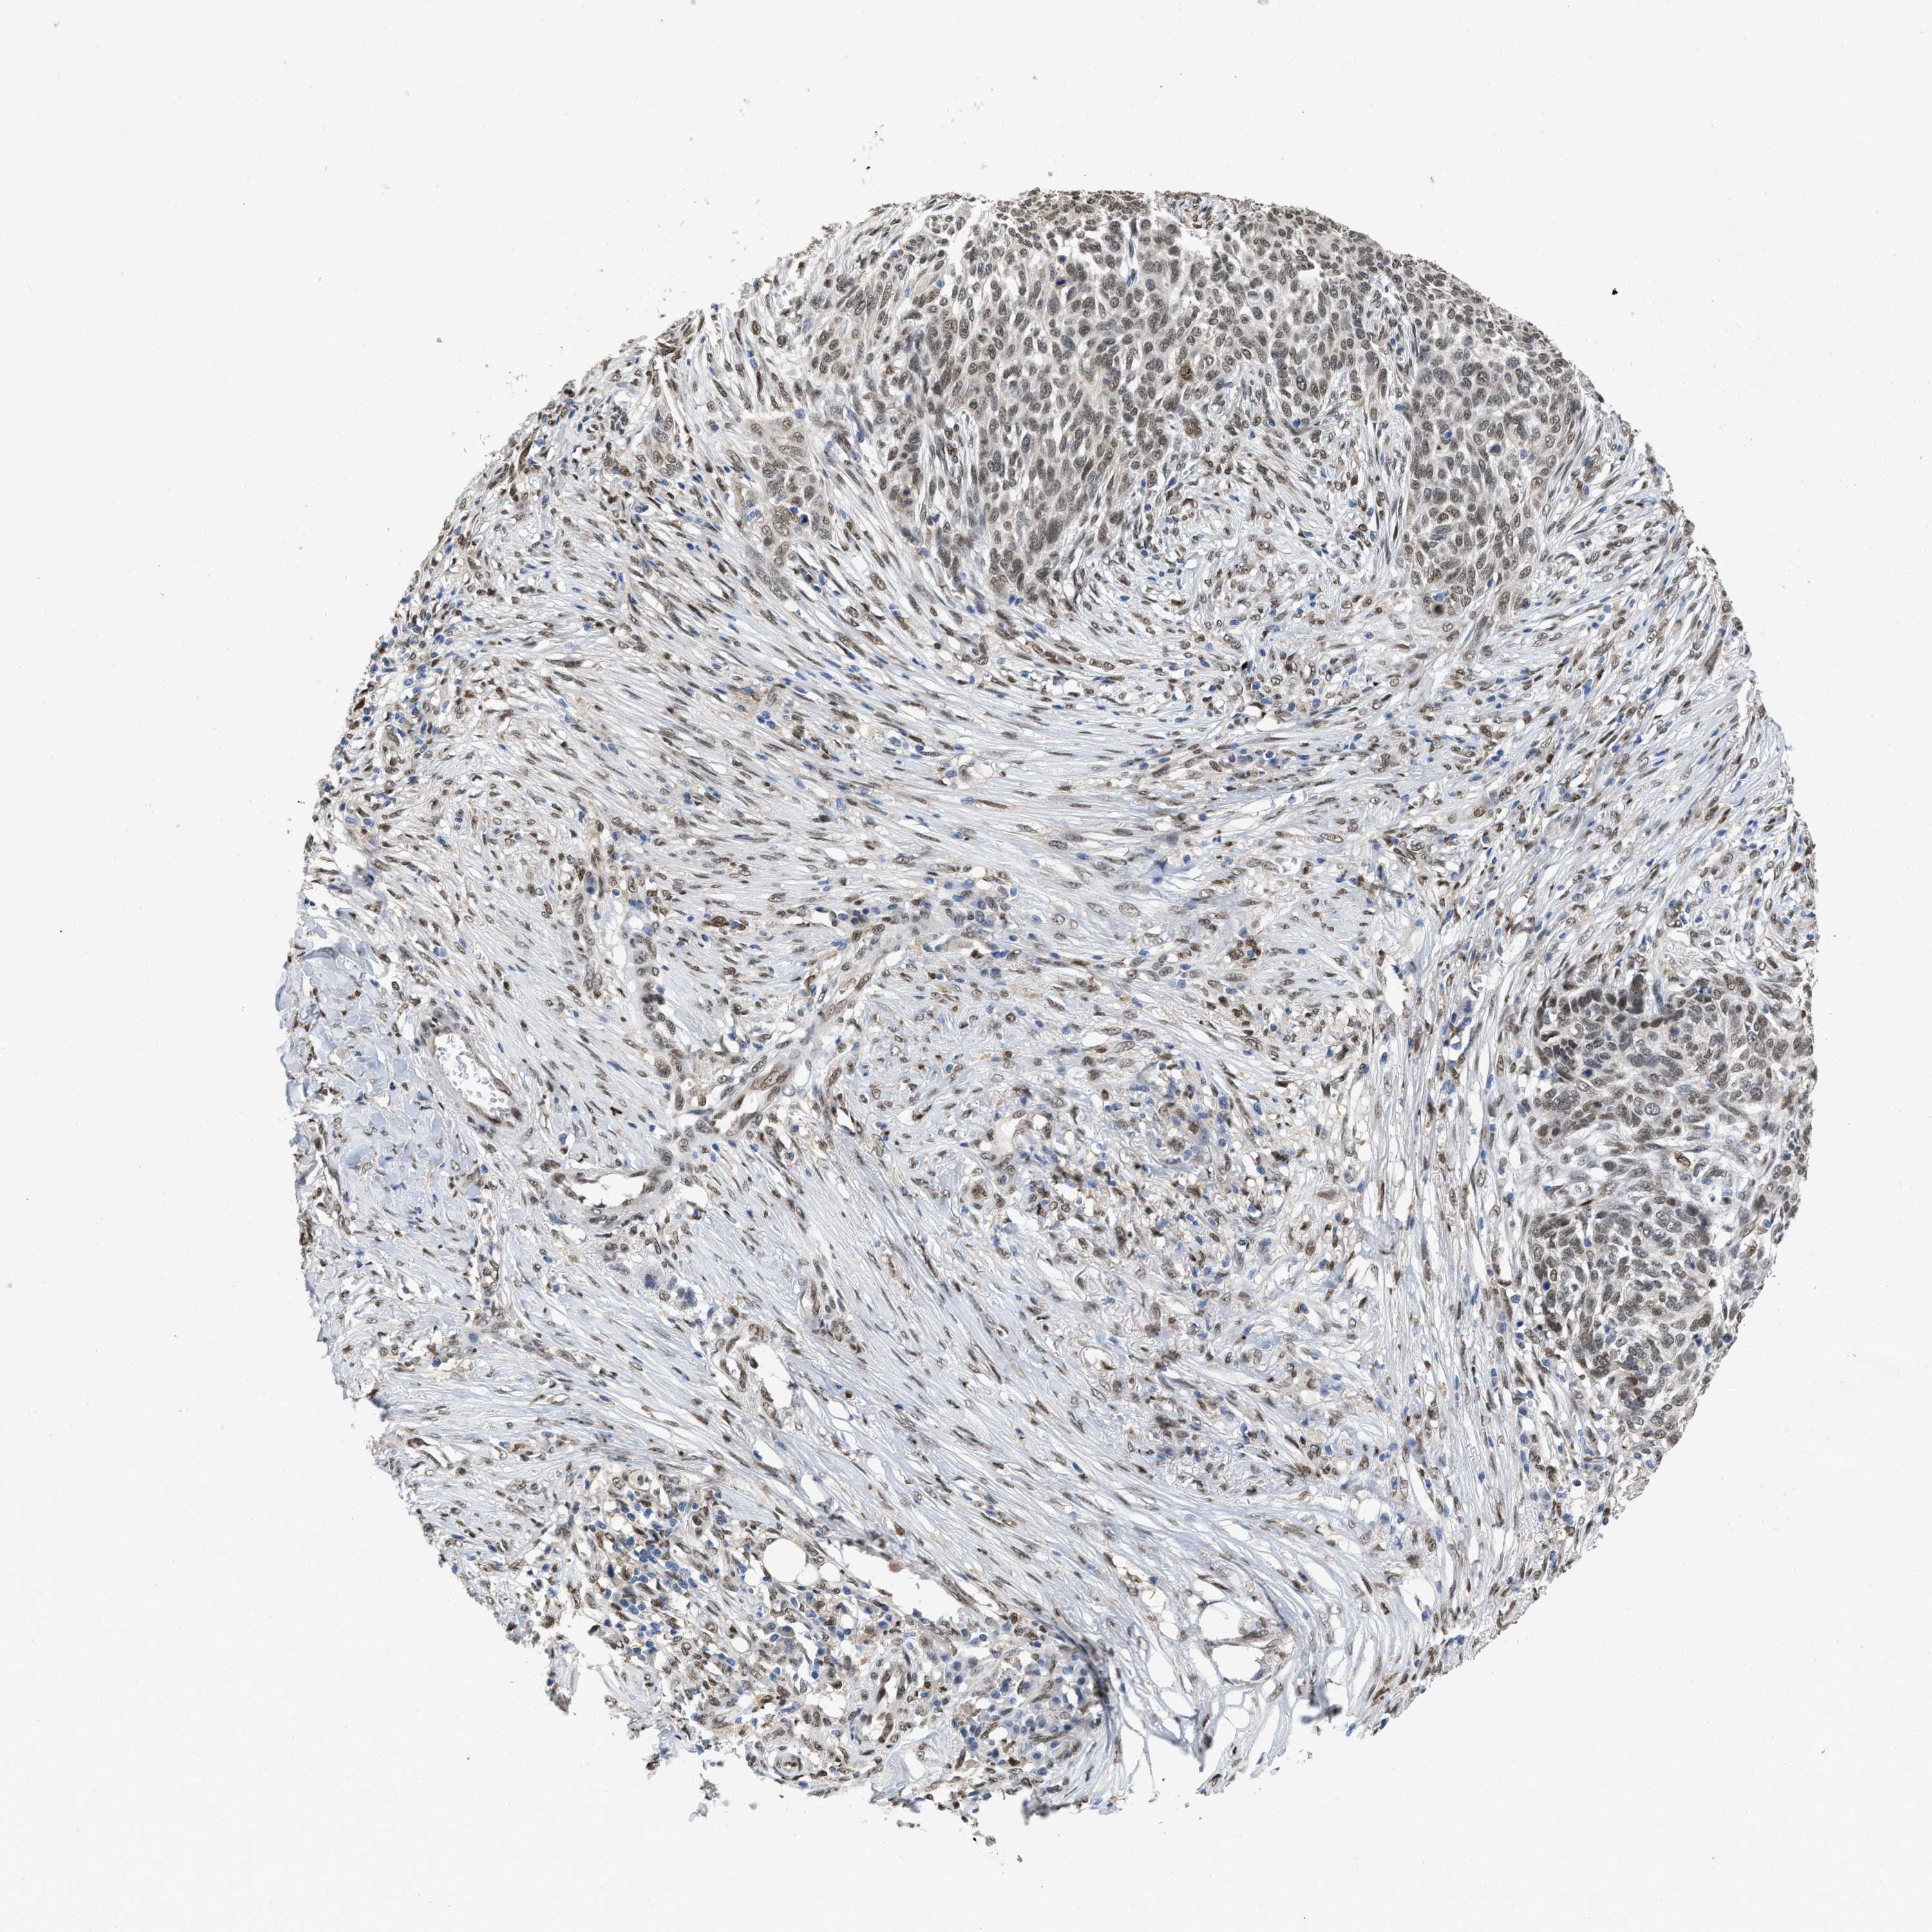

SKIN CANCER - Protein expressioni

A mouse-over function shows sample information and annotation data. Click on an image to view it in a full screen mode. Samples can be filtered based on level of antibody staining by selecting one or several of the following categories: high, medium, low and not detected. The assay and annotation is described here.

Each image is clickable and will lead to virtual microscopy that enables deeper exploration of all samples and also displays staining intensity scores, fraction scores and subcellular localization as well as patient and tissue information for each sample.

Antibody HPA019123

Staining

High

Medium

Low

Not detected

Intensity

Strong

Moderate

Weak

Negative

Quantity

>75%

75%-25%

<25%

None

Location

Nuclear

Cytoplasmic/membranous

Cytoplasmic/membranous,nuclear

Squamous cell carcinoma, NOS

Squamous cell carcinoma, metastatic, NOS